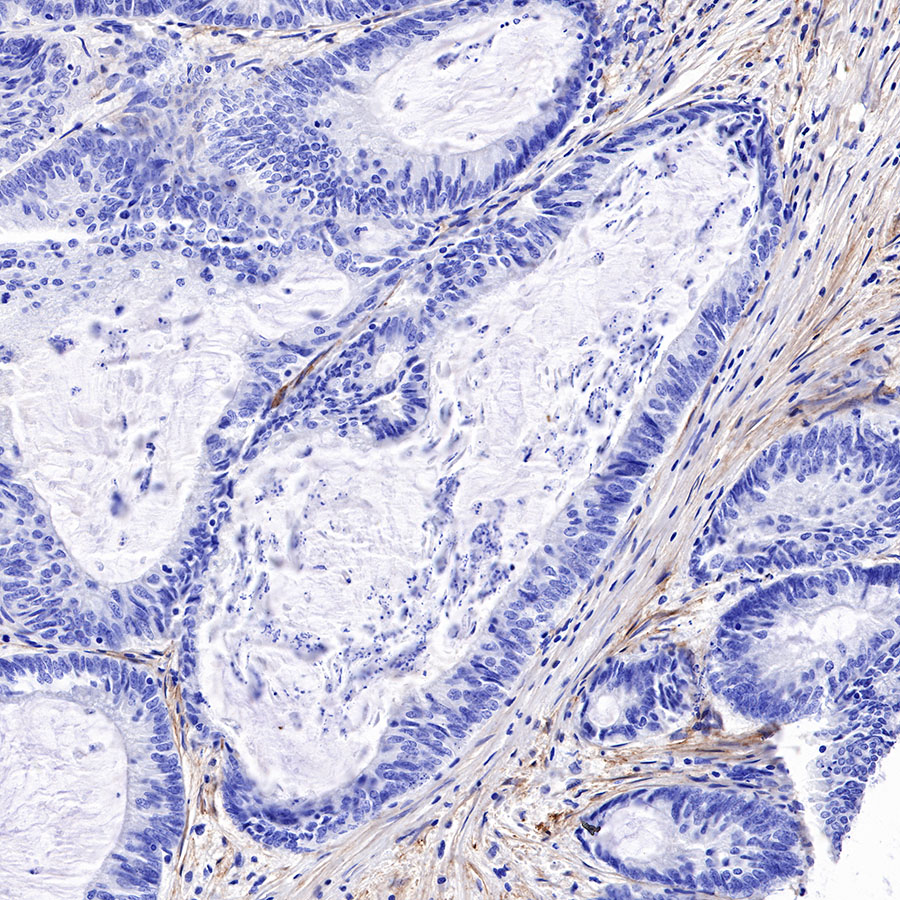

Immunohistochemistry

IHC shows positive staining in paraffin-embedded human lung squamous cell carcinoma. Anti-FAP antibody was used at 1/500 dilution, followed by a HRP Polymer for Mouse & Rabbit IgG (ready to use). Counterstained with hematoxylin. Heat mediated antigen retrieval with Tris/EDTA buffer pH9.0 was performed before commencing with IHC staining protocol.